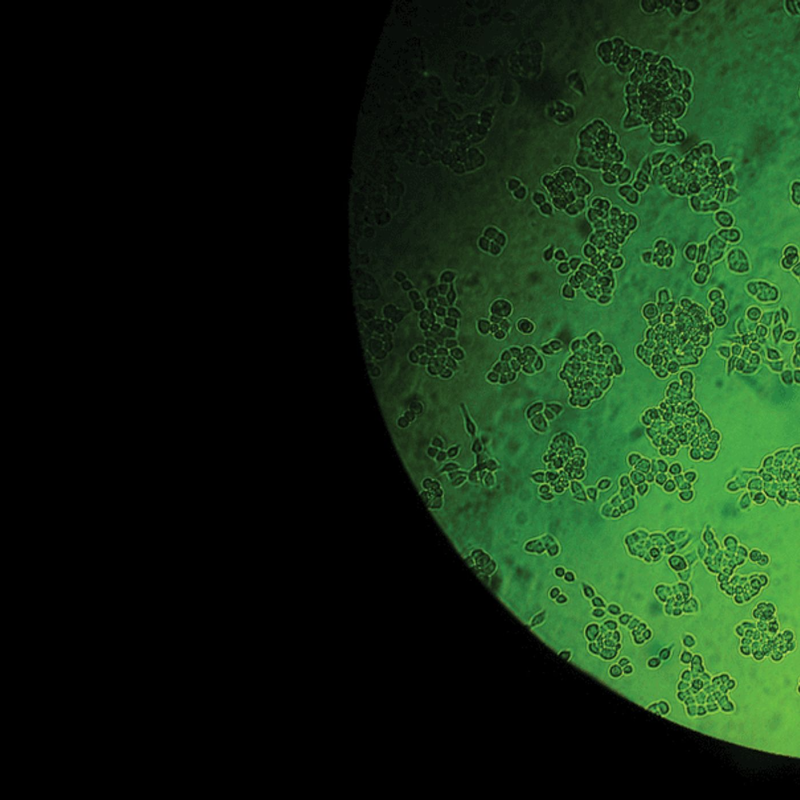

With all the recent talk about HBO's upcoming film, we decided it would be good time to re-run our story of one woman's medically miraculous cancer cells, and how Henrietta Lacks changed modern science and, eventually, her family's understanding of itself.